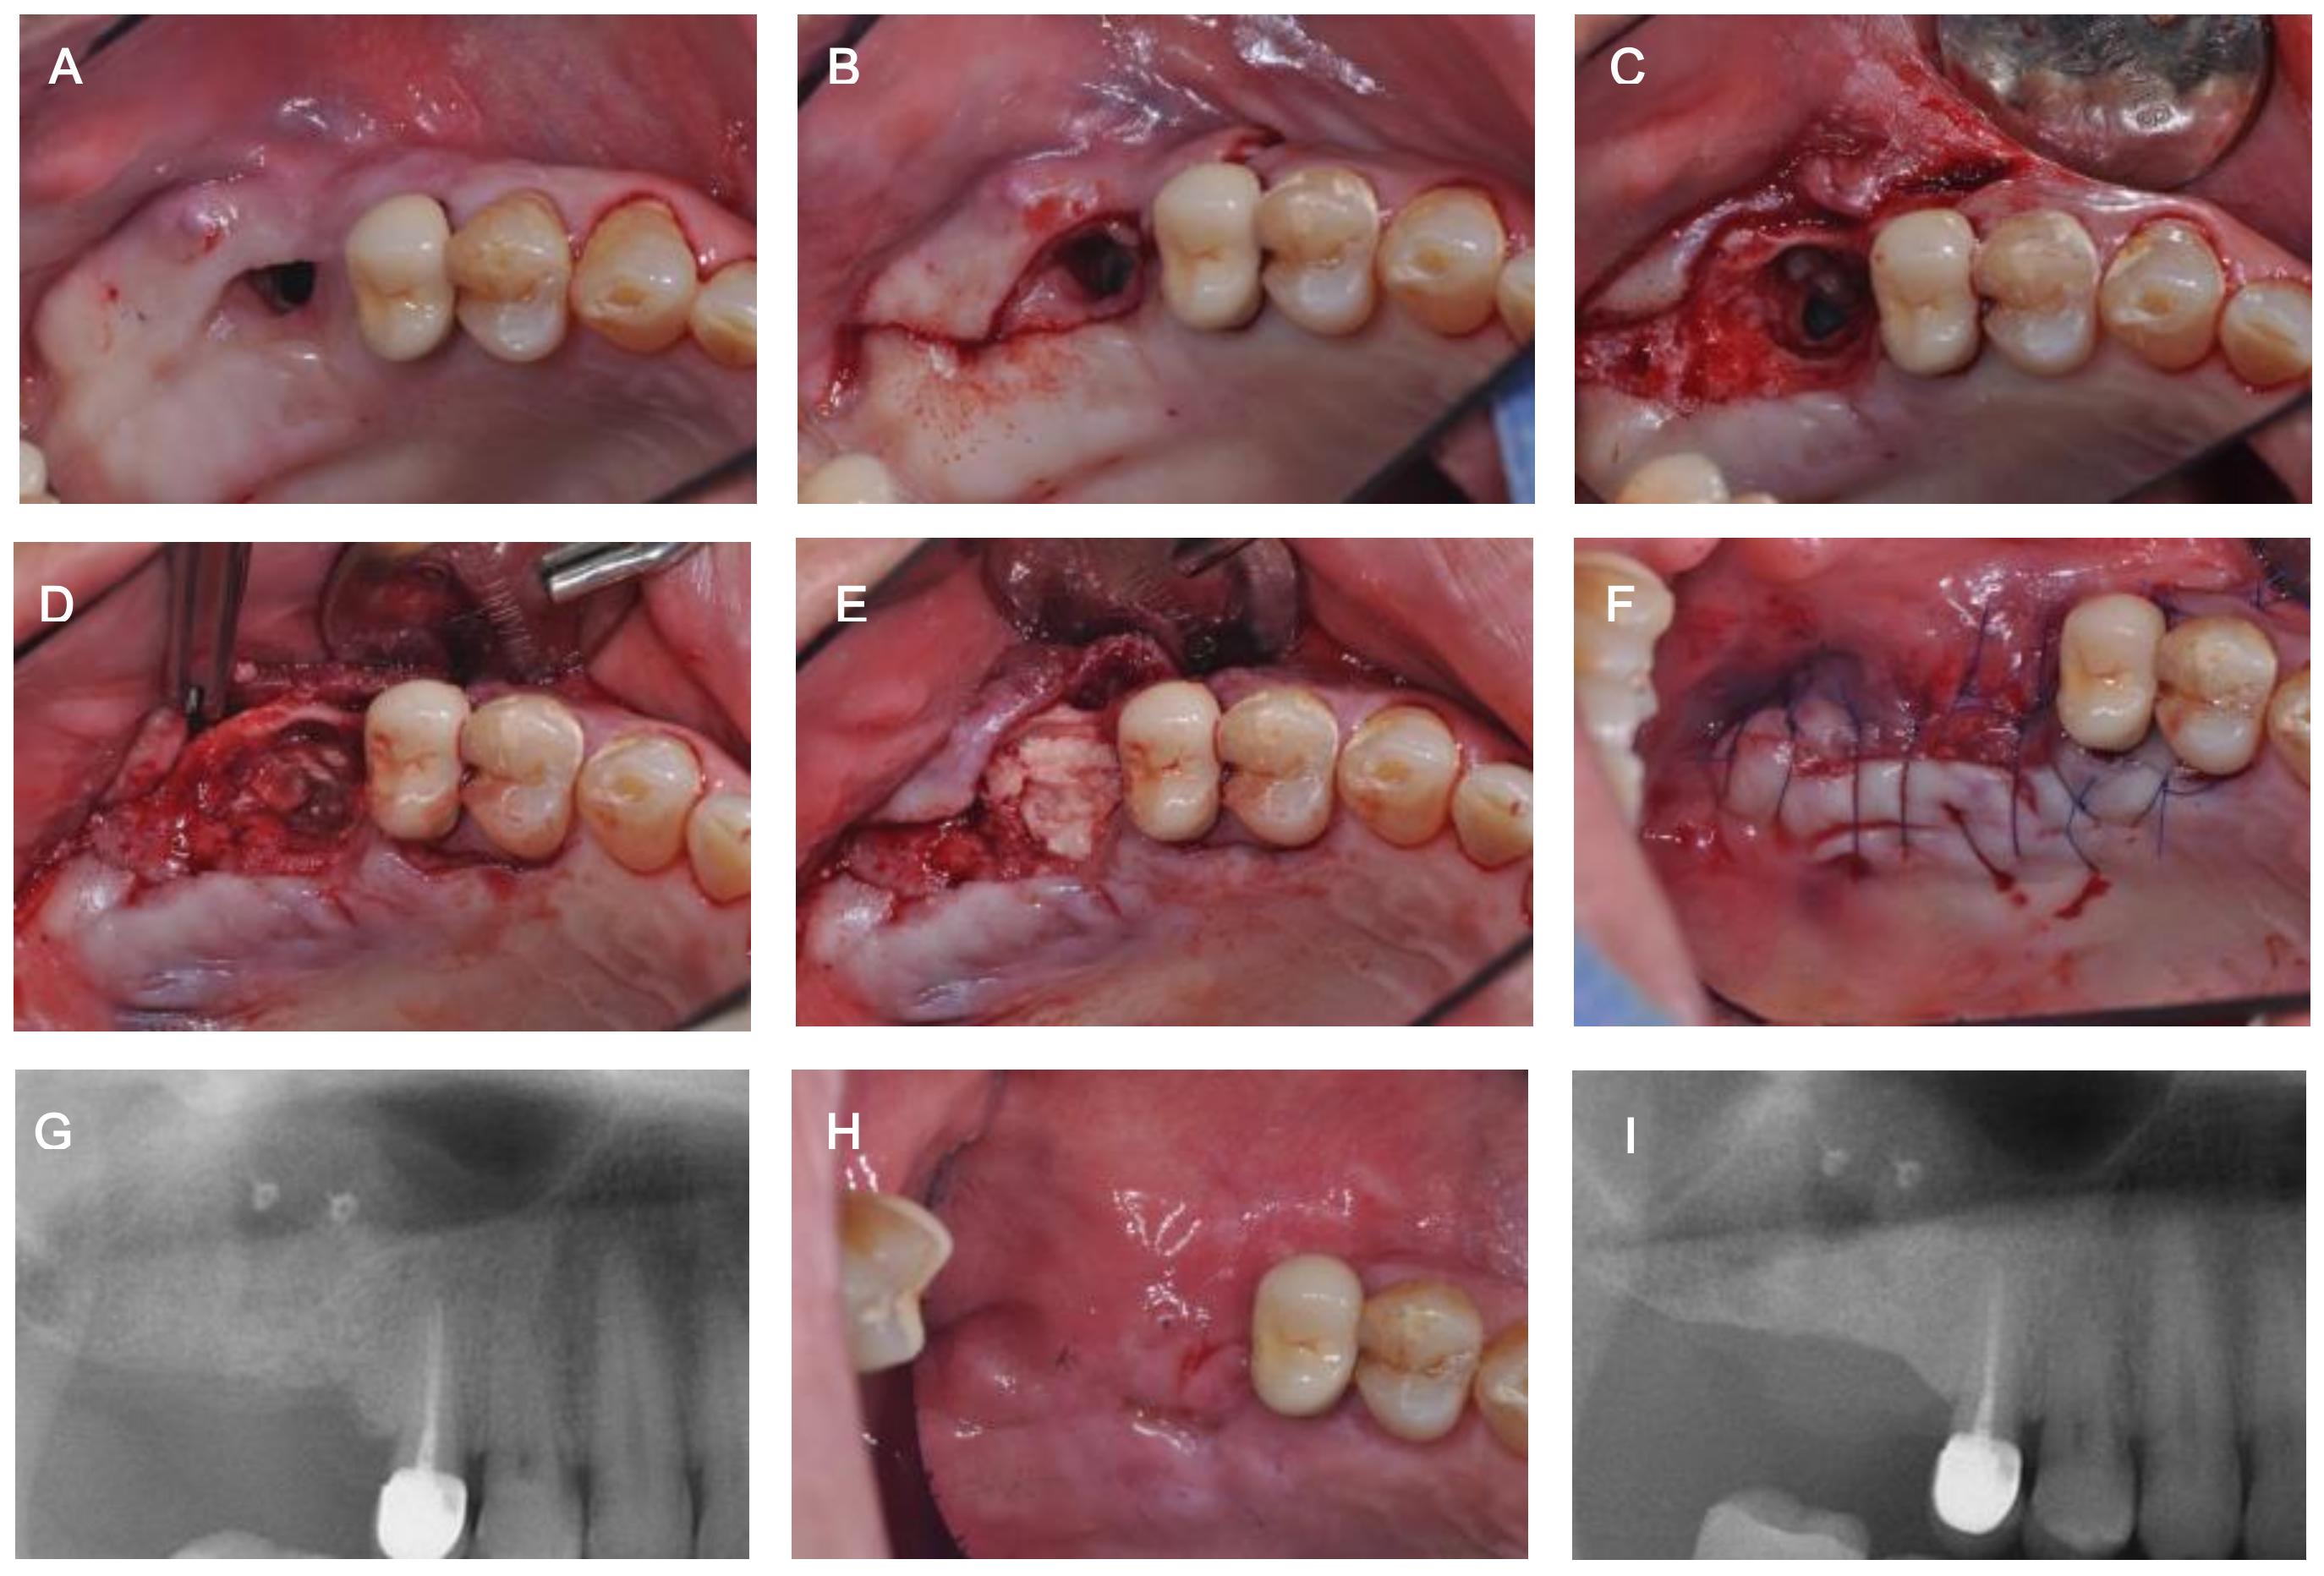

2. Case Description